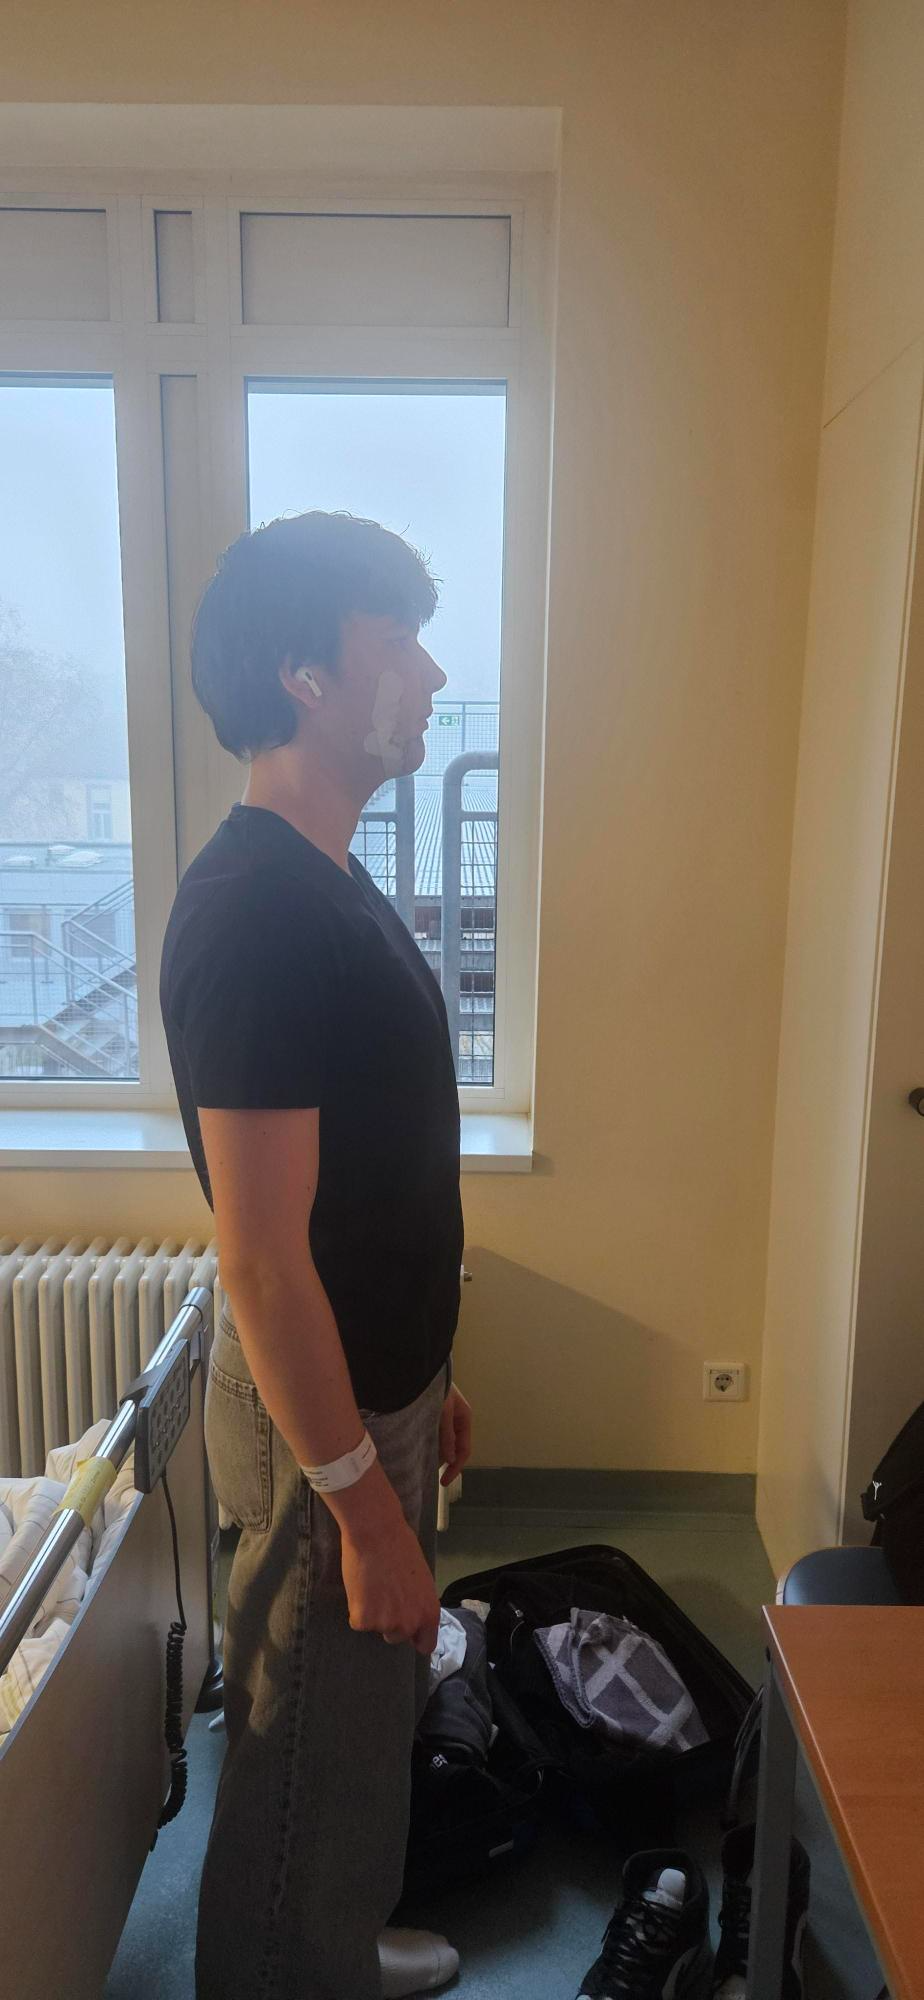

After pictures:

As you can see i'm still very bloated. My question is: How much do yall think i will ascend? How much of an impact will it have once the bloat is gone?

After pictures:

As you can see i'm still very bloated. My question is: How much do yall think i will ascend? How much of an impact will it have once the bloat is gone?